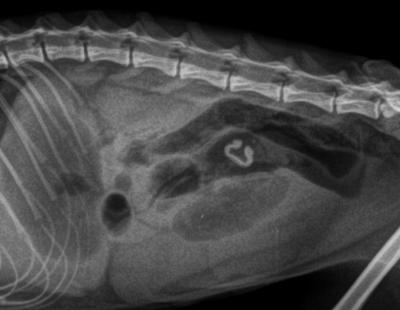

V tomto případě byla naopak identifikace cizího tělesa na RTG snímku velice obtížná - struktura náplně střeva ukazovala na přítomnost hadry či něčeho podobného ve střevě (na snímku se zobrazuje téměř neznatelně, má podobnou strukturu jako otisk mycí houby).